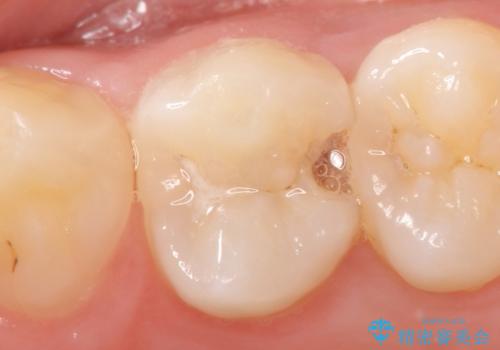

セラミックインレー 虫歯で欠けた歯の治療